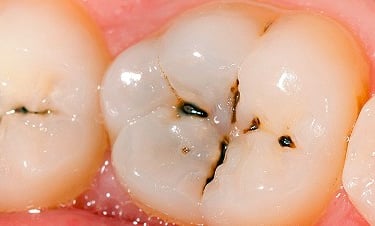

Pulpitis Reversible

La pulpitis reversible es una inflamación leve de la pulpa dental, generalmente causada por caries o una lesión menor.

Los pacientes suelen experimentar sensibilidad al frío o al calor, pero el dolor desaparece rápidamente.

Si se trata adecuadamente, la pulpa puede sanar sin complicaciones. Es importante acudir al dentista para evitar que progrese a una pulpitis irreversible.